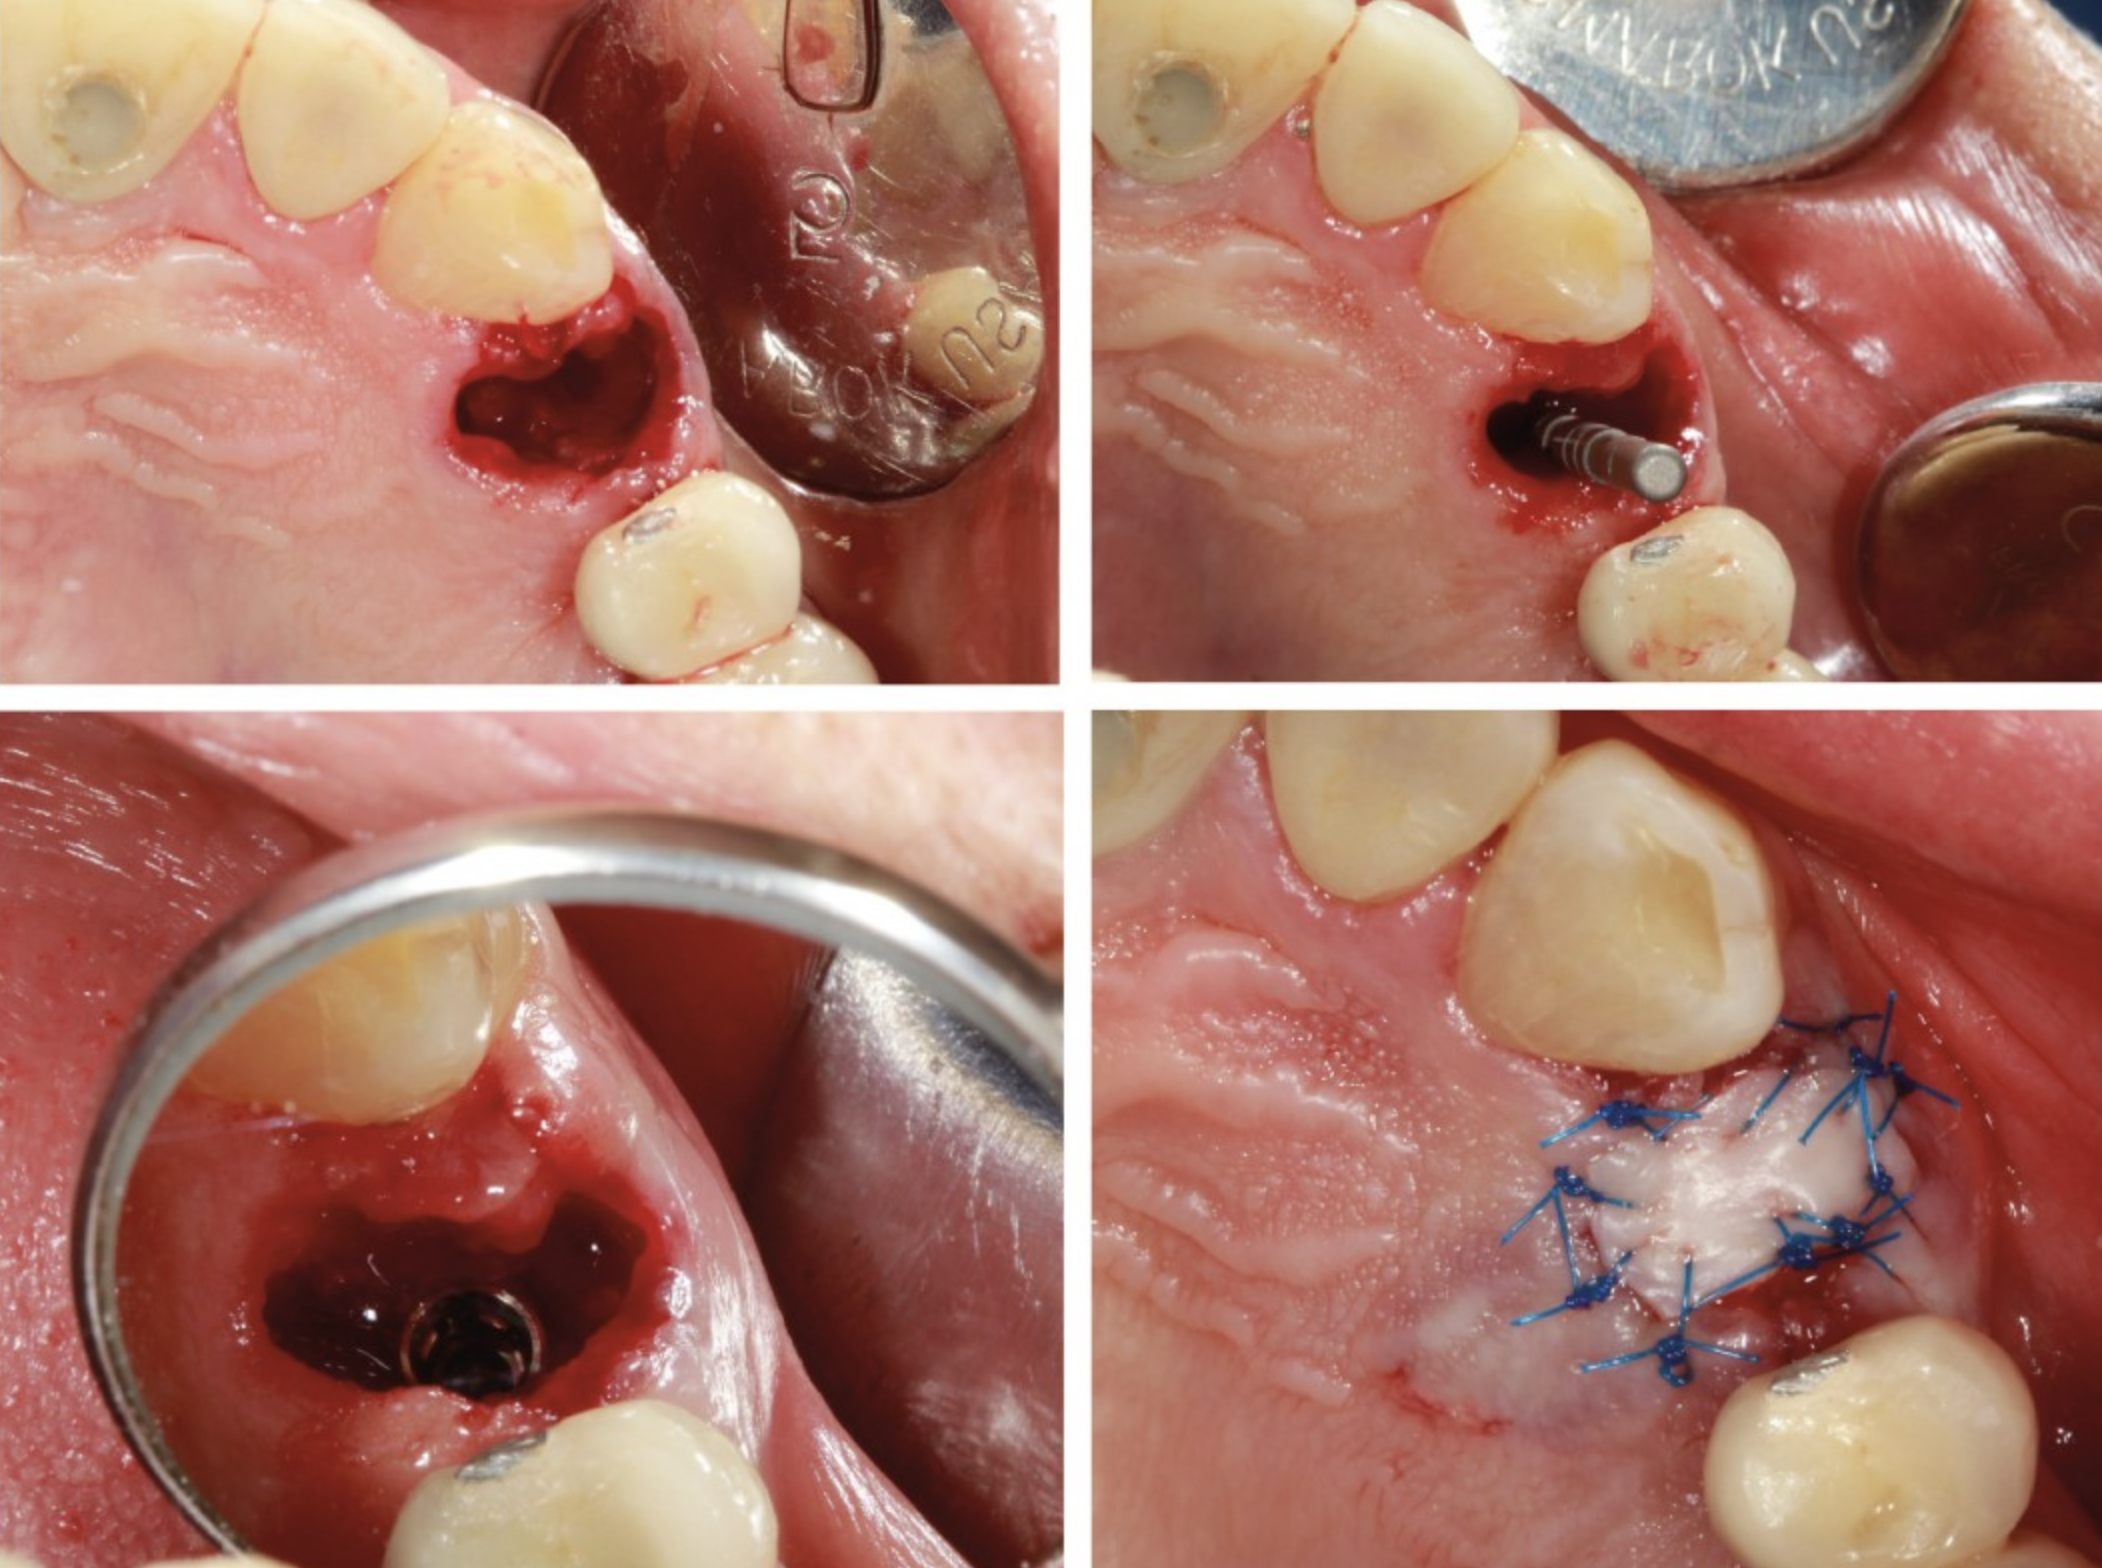

Proceso de Rehabilitación Paso a Paso

- Evaluación y Diseño Digital

Se realiza un escaneo intraoral o toma de impresión digital de los implantes y tejidos.

- Selección del Pilar Protésico (Abutment)

Es el conector entre el implante y la restauración, estos pueden ser:

- Colocación de la Restauración Definitiva: La prótesis puede ser cementada o atornillada, dependiendo del caso clínico.

- Las restauraciones atornilladas facilitan el mantenimiento y el acceso al implante.

- Las cementadas ofrecen un acabado más estético en algunos casos anteriores.